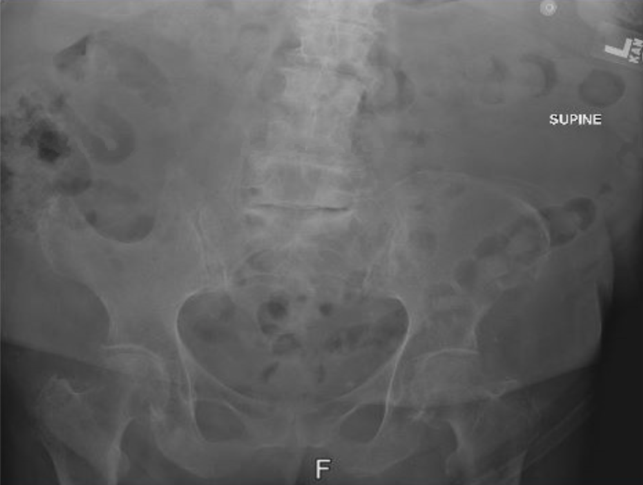

Diagnostic tests. Right hip and pelvic radiographs were obtained, which demonstrated a large bone defect involving the right iliac wing with associated degenerative arthritic changes (Figure 1).

Figure 1. Pelvic radiograph showing a large bone defect involving the right iliac wing.